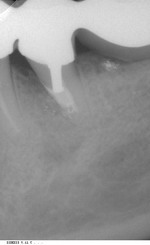

Röntgenbefund (Abb. 3)

Die Auswertung der intraoralen Röntgenaufnahme der Zähne 34 und 35 ergibt folgenden Befund:

q       Die Zähne 34 und 35 sind mit verblendeten Kronen und höchstwahrscheinlich intrakanalären Metallstiften versorgt. Es ist nicht eindeutig erkennbar, ob die Kronen mit den Stiften verbunden sind. Aufgrund der röntgenologisch erkennbaren  Konizität und der apikalen Geometrie der Stifte kann vermutet werden, dass es sich um zementierte Parapost-Stifte handelt.

q       Die Randdichtigkeit der Kronen scheint akzeptabel zu sein

q       Die Zähne 34 und 35 sind endodontisch behandelt und zeigen suboptimale Wurzelkanalfüllungen, die ca. 2 mm vor dem anatomischen Apex enden;

q       Der Stift in Zahn 34 erscheint zentral im Wurzelkanal platziert zu sein und reicht bis in das koronale Drittel des Wurzelkanals;

q       Die Insertionsachse des Stiftes im Zahn 35 weicht stark nach mesial von dem gefüllten Kanallumen ab. Die Spitze des Stiftes reicht bis in das mittlere Wurzelkanaldrittel und endet ca. 0,5 mm vor der mesialen Wurzelkanalwand.

q       Ausgedehnte mesiale pararadikuläre Aufhellung (6 X 13mm) im koronalem und mittlerem Bereich der Wurzel des Zahnes 35.